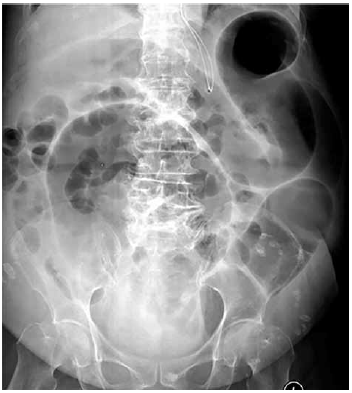

Mulher de 85 anos, com histórico de demência, é tratada com antibiótico oral para infecção urinária. Cerca de 5 dias depois, ela evolui com queda do estado geral e diarreia aquosa. Exame físico: desidratada 3+/4; pressão arterial: 92 x 58 mmHg; frequência cardíaca: 105 bpm; cardiopulmonar sem alteração relevante; abdome: distendido com dor difusa à palpação e redução dos ruídos intestinais; toque retal sem melena ou hematoquezia. Exames séricos: hemoglobina: 12,1 g/dL; leucócitos: 12 200/mm3; plaquetas: 254 000/mm3; proteína C reativa muito elevada; creatinina: 1,3 mg/dL. Hemoculturas são coletadas, assim como exames fecais. A radiografia de abdome é mostrada a seguir.